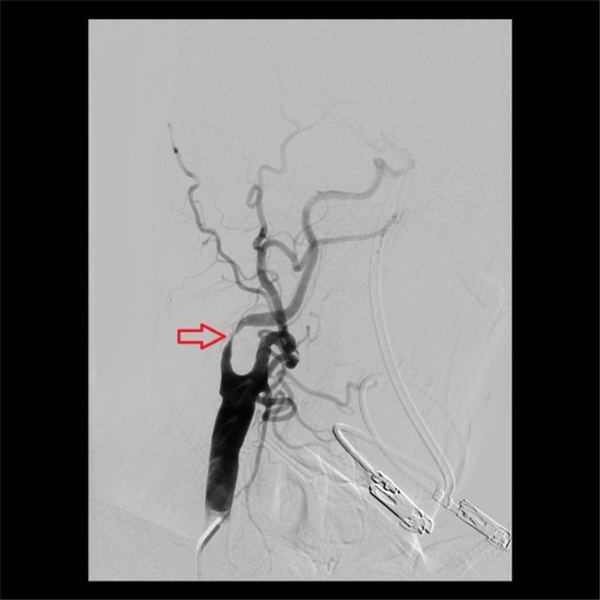

术后再次造影显示,右侧颈内动脉支架位置好,膨胀充分,血流通畅,颅内血管未见异常(上图红色箭头所示)。